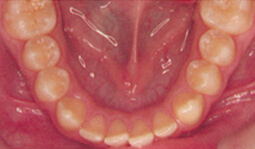

Ein Sechs-Punkt-Reatiner

stabilisiert die Zähne nach

umfangreichen Zahnbewegungen.

Der meist angewendete Retainer aus „verseiltem Draht“

Grazil und unsichtbar auf der Zungen- oder Gaumenseite

der Zähne mit einem Spezialkunststoff befestigt – Komfort und Sicherheit zugleich.

Die aus dünnem, sechsfach verseiltem Draht hergestellten „Retainer“ stören weder beim Sprechen noch beim Essen und machen keinerlei Beschwerden. Sie halten die Zähne an ihrem neuen Platz, damit sie dort wieder fest in den Kieferknochen einwachsen. Umso größer die vorausgegangene Zahnbewegung war, desto länger muss der Retainer getragen werden.